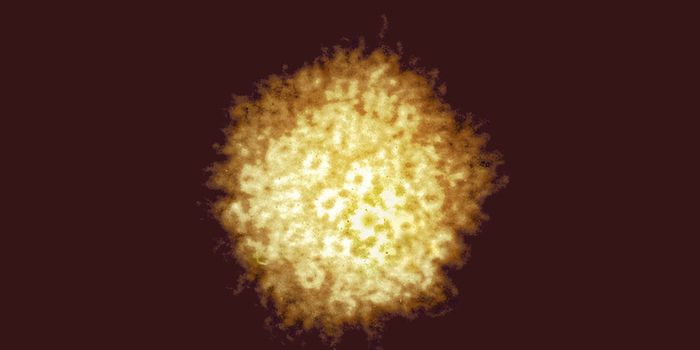

JAN 28, 2025CancerHuman papillomavirus (HPV) encompasses over 200 viruses, many spreading through sexual contact. Twelve strains of ...

JAN 09, 2025Cannabis SciencesA new in vitro study found that cannabidiol (CBD) may effectively treat colorectal cancer, regardless of mutation.

JAN 05, 2025Cell & Molecular BiologyThere is mounting evidence that links neurodegenerative diseases and viral infections, such as the association between m ...

JAN 02, 2025ImmunologyCancer is an umbrella term used to characterize the abnormal growth of cells in different organs and tissues. Specific c ...

DEC 26, 2024ImmunologyMillions of individuals are affected by cancer each year. In response, different organizations and the federal governmen ...

DEC 22, 2024CancerTriple-negative breast cancer (TNBC) remains one of the most aggressive types of breast cancer. Determined by a la ...

DEC 12, 2024ImmunologyVaccines have advanced the field of health and medicine throughout the last century. They are commonly given before a di ...

DEC 12, 2024ImmunologyImmunotherapy has changed the way physicians treat patients and has improved standard of care for many different tumors. ...

DEC 10, 2024Drug Discovery & DevelopmentA novel immunotherapy for breast cancer produced fewer side effects than currently-used chemotherapy regimens in a recen ...

DEC 09, 2024CancerCancer cells have evolved sophisticated strategies to evade the immune system, prolonging their survival and growth.&nbs ...

DEC 05, 2024ImmunologyTreatment for solid tumors has improved in the last two decades with the emergence of immunotherapy. Immunotherapy is a ...

DEC 02, 2024CancerImmunotherapies have shaped the cancer research space over the past decade, proving effective for the treatment of some ...

NOV 28, 2024ImmunologyMillions of people around the world are diagnosed with cancer each year. The rapid proliferation of mutated cells can fa ...

NOV 28, 2024ImmunologyCancer is a disease in which mutated cells grow rapidly and uncontrollably. Unfortunately, these cells resist the body&r ...